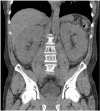

Amyloidosis comprises a rare spectrum of protein deposition diseases that diffusely or focally affect any organ. Amyloid's variable clinical presentation and nonspecific disease course often cause it to evade early diagnosis. This pictorial essay aims to familiarize radiologists with the pathophysiology of amyloidosis, to describe the basic classifications of amyloidosis, and to use multimodality imaging to illustrate its varied appearance throughout the body. This review highlights the diagnostic challenge of interpreting radiographic studies in patients with hematologic malignancies and concurrent amyloidosis. Radiologists should consider amyloid in chronically ill patients or patients with hematologic malignancies who have unusual/unexpected imaging findings.